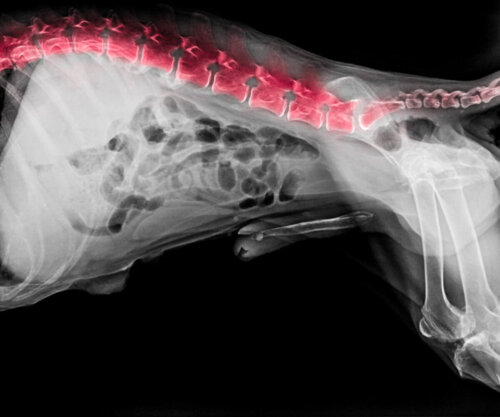

Podobnie jak ludzie, psy są również podatne na choroby i wady rozwojowe, które zmieniają równowagę w ich jakości życia. Problemy z kręgosłupem u psów są jednym z głównych i najbardziej dokuczliwych procesów, przez które przechodzą te zwierzęta i bez wątpienia należy je odpowiednio wcześnie wyleczyć.

Jak mogłeś zauważyć, problemy z kręgosłupem u psów są do siebie bardzo podobne. Dlatego korzystanie z narzędzi diagnostycznych będzie bardzo pomocne w zdefiniowaniu procesu, przez który przechodzi Twój zwierzak. Główne i najskuteczniejsze metody diagnostyczne stosowane obecnie w klinikach to:

- Urządzenia rentgenowskie (z kontrastem lub bez).

- Tomografia komputerowa.

- Rezonans magnetyczny.

- Pobieranie próbek (płyn mózgowo-rdzeniowy).